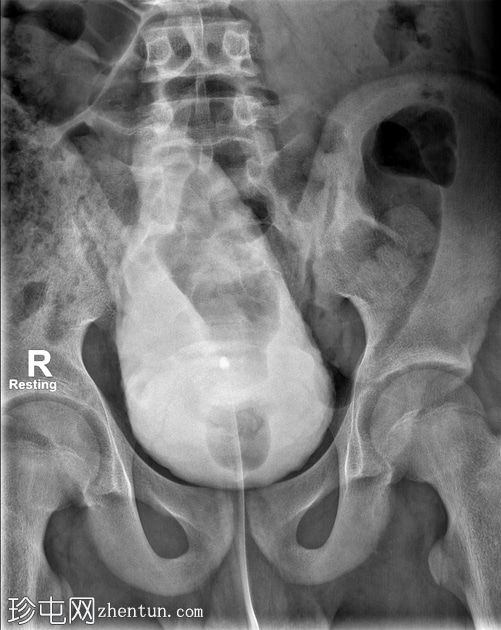

荧光透视

正面

静息

通过导尿管注入造影剂后,可见膀胱延长,膀胱壁不规则,呈小梁状,并有多个大小不一的外囊。

排尿后序列中可见残余尿液。

本病例展示了

神经

源性膀胱的临床和放射学特征。